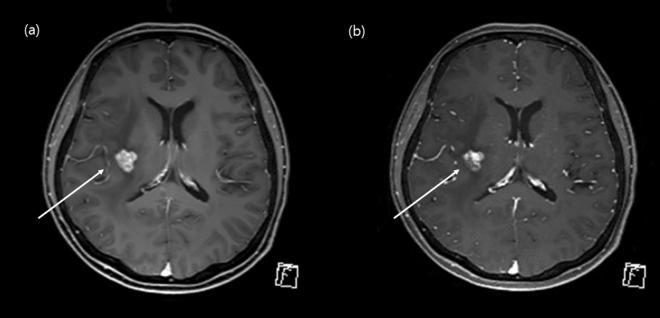

Our objective was to evaluate and compare the diagnostic performance of post-contrast 3D compressed-sensing volume-interpolated breath-hold examination (CS-VIBE) and 3D T1 magnetization-prepared rapid-acquisition gradient-echo (MPRAGE) in detecting intracranial metastasis. Additionally, we analyzed and compared the image quality between the two. We enrolled 164 cancer patients who underwent contrast-enhanced brain MRI. Two neuroradiologists independently reviewed all the images. The signal-to-noise ratio (SNR), contrast-to noise ratio (CNR) were compared between two sequences. For patients with intracranial metastasis, we measured enhancement degree and CNR of the lesion. The overall image quality, motion artifact, gray-white matter discrimination and enhancing lesion conspicuity were analyzed. Both MPRAGE and CS-VIBE showed similar performance in diagnosing intracranial metastasis. Overall image quality of CS-VIBE was better with less motion artifact; however conventional MPRAGE was superior in enhancing lesion conspicuity. Overall, the SNR and CNR of conventional MPRAGE were higher than those of CS-VIBE. For 30 enhancing intracranial metastatic lesions, MPRAGE showed a lower CNR (p = 0.02) and contrast ratio (p = 0.03). MPRAGE and CS-VIBE were preferred in 11.6 and 13.4% of cases, respectively. In comparison with conventional MPRAGE, CS-VIBE achieved comparable image quality and visualization, with the scan time being half of that of MPRAGE.

我们的目的是评估和比较对比增强后 3D 压缩感知容积内插屏气检查(CS-VIBE)和 3D T1 磁化准备快速获取梯度回波(MPRAGE)在检测颅内转移中的诊断性能。此外,我们还分析和比较了这两种方法的图像质量。我们纳入了 164 例接受增强脑 MRI 的癌症患者。两名神经放射科医生独立审查了所有图像。比较了两种序列的信噪比(SNR)和对比噪声比(CNR)。对于有颅内转移的患者,我们测量了病变的增强程度和 CNR。分析了整体图像质量、运动伪影、灰-白质分辨力和增强病变的显著度。MPRAGE 和 CS-VIBE 在诊断颅内转移方面均具有相似的性能。CS-VIBE 的整体图像质量更好,运动伪影更少;然而,常规 MPRAGE 在增强病变的显著度方面更优。总体而言,常规 MPRAGE 的 SNR 和 CNR 均高于 CS-VIBE。对于 30 个增强的颅内转移病变,MPRAGE 显示出较低的 CNR(p=0.02)和对比比(p=0.03)。MPRAGE 和 CS-VIBE 分别在 11.6%和 13.4%的病例中更受青睐。与常规 MPRAGE 相比,CS-VIBE 实现了可比的图像质量和可视化效果,扫描时间仅为 MPRAGE 的一半。